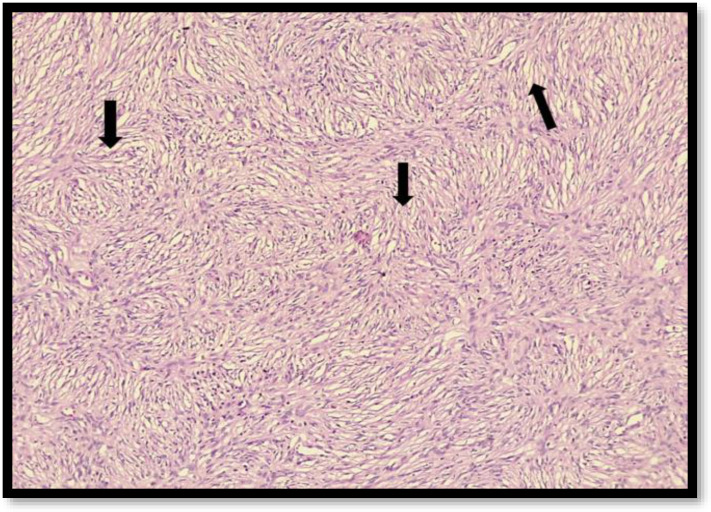

Objective: Dermatofibrosarcoma protuberans (DFSP) of the vulva is an uncommon soft tissue tumor with fewer than 60 cases reported previously. Distant metastasis is rare with a high propensity for local invasion. Surgical management is the gold standard with adequate margin excision to prevent future recurrences. We report a case of vulvar DFSP requiring three resections to achieve primary clearance. To the best of our knowledge, this is the first case report from India. Case report : A 35-years-old female, presented with nodular vulvar mass for the third time arising from the upper part of right labia majora for the last year. She had a history of two similar episodes in the past for which excision was done and histopathology confirmed DFSP. The third wide local resection was performed with 3 cm margins and the margins were sent for intra-operative frozen section analysis, which was confirmed clear by the pathologist. The patient has been free of recurrence for two years. Conclusion: DFSP is a challenging condition presenting as a non-tender nodular mass characterized by local invasion and recurrence. Early diagnosis and appropriate management using wide local excision with accurate margin assessment can achieve optimal results and prevent future recurrences.